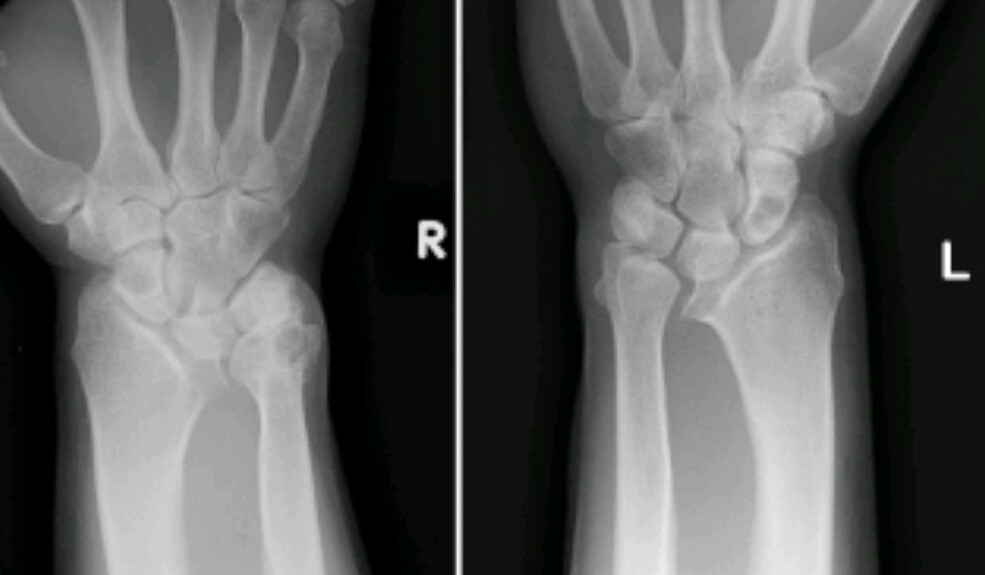

Findings? Diagnosis?

Geographic, central, oval radiolucency with long axis parallel to bone

POSSIBLE FALLEN FRAGMENT SIGN, OPEN GROWTH PLATES

Solitary bone cyst